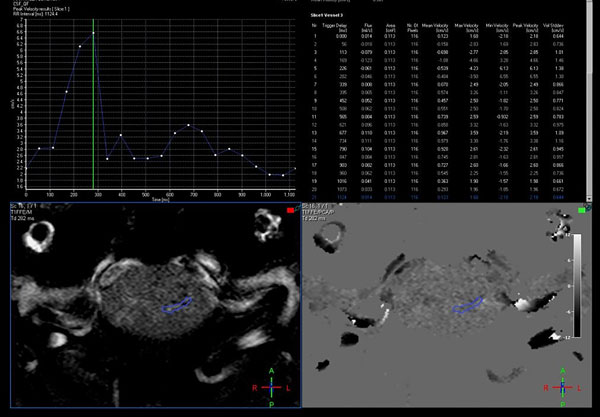

Estas secuencias permiten una evaluación cualitativa con valoración subjetiva del pasaje del LCR a través de las cisternas (Figura 1) y una valoración cuantitativa de la velocidad (Figura 2). La adquisición de las mismas se realiza de forma coordinada con el latido cardíaco (gatillado mediante el censado por el electrocardiograma o curva de pulso).13

La valoración cuantitativa requiere un postproceso para medición de flujo en estaciones de trabajo con software dedicado, las cuales permiten la evaluación de la curva obtenida durante todo el ciclo cardíaco, que es característicamente bifásica, con los respectivos cálculos de los valores de velocidad pico, media y stroke volume.

Figura 2: Evaluación cuantitativa en RM con técnica de contraste de fase, mediante la adquisición en el plano axial, perpendicular al sitio de mayor compromiso del pasaje de LCR, con un área de interés que muestra las curvas de flujo y un aumento de la velocidad pico hasta 6,55 cm/segundo.